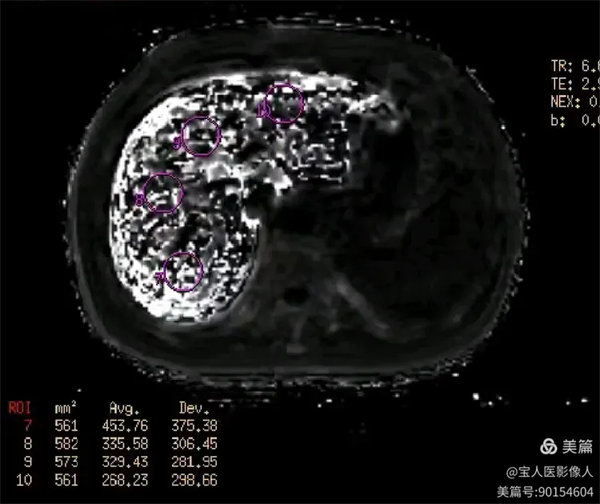

R2*圖,測量全肝不同部位肝實質的R2*值都明顯升高。